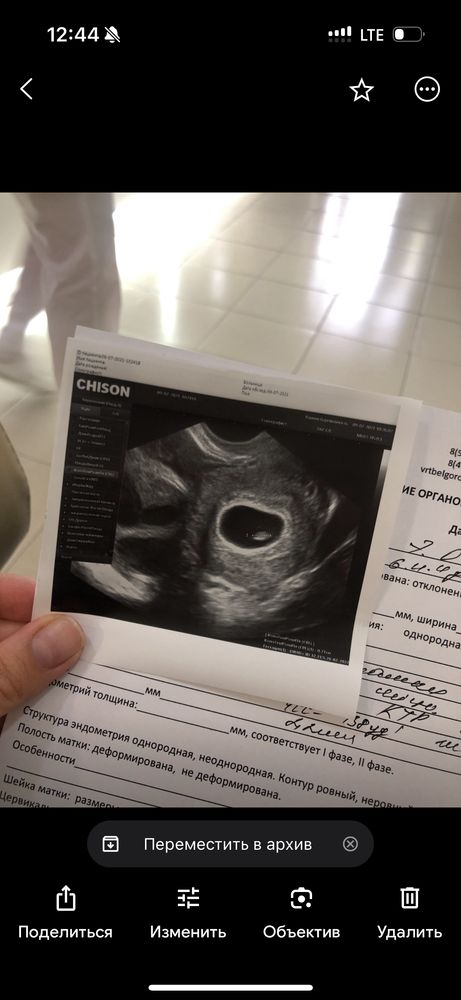

Не поленилась нашла свое на 27 дпп ,ктр 0,71 Изображение

квитка, ну вот у тебя на 30 дпп, КТР наверное был уже 10

Очень интересно))) УЗИ 40 дпп